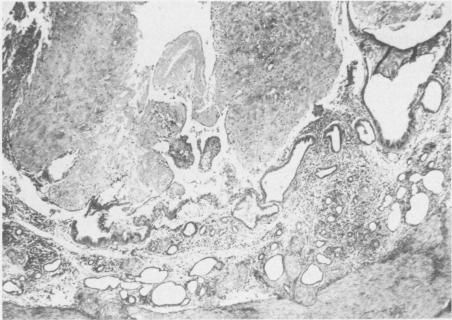

Ninety-eight reproductive tracts from dogs at different postpartum time periods were used to investigate stages of normal involution. Seventy-eight reproductive tracts were obtained from the field, and 20 obtained surgically for gross and microscopic examination. Plasma progesterone was measured in 22 dogs at various times postpartum. The uterine horns during the first week postpartum were dilated and edematous. The placental sites were 1.5-3 cm in width, rough, granular and covered with mucus and a few blood clots. By the fourth week the placental sites were thick, grayish-tan and nodular with a few blood clots within nodules. The uterine horns during the seventh week were greatly contracted and the placental sites were narrow and light in color. A few nodules were still present on the surface. By the ninth week the uterine horns were uniform in shape and contracted with a narrow lumen. The placental sites appeared as a narrow brown band. Histologically the placental sites during the first week postpartum were covered by an eosinophilic staining necrotic mass and a few intact epithelial cells scattered on the surface as an interrupted single layer. Under the necrotic mass, large eosinophilic staining cells in moderate number were scattered throughout the lamina propria of the placental site. These cells were considered to be decidual cells. By the fourth week the placental sites were covered by a large lobulated mass of collagen fibers. The uterine glands were greatly dilated and degenerate, and mononuclear cell infiltration in the lamina propria was pronounced. By the seventh week, large masses of collagen fibers were detached from the surface, and endometrial glands were normal in size and shape. By the ninth week surface sloughing was completed. However, regeneration and replacement of the endometrial lining from the mouth of the uterine glands continued until the end of the twelfth week when the involution process was completed. The progesterone levels were very low for eight weeks postpartum.

98条处于不同产后时期的犬生殖道用于研究正常 involution 的阶段。78条生殖道取自野外,20条通过手术获取用于大体和显微镜检查。在产后不同时间对22只犬测量血浆孕酮。产后第一周子宫角扩张且水肿。胎盘部位宽1.5 - 3厘米,粗糙、呈颗粒状,覆盖有黏液和少量血凝块。到第四周时,胎盘部位增厚,呈灰棕色且有结节,结节内有少量血凝块。第七周时子宫角大幅收缩,胎盘部位变窄且颜色变浅。表面仍有一些结节。到第九周时,子宫角形状均匀且收缩,管腔狭窄。胎盘部位呈现为一条狭窄的棕色带。组织学上,产后第一周的胎盘部位被嗜酸性染色的坏死物质覆盖,表面有一些完整的上皮细胞散在分布,形成间断的单层。在坏死物质下方,中等数量的大嗜酸性染色细胞散在分布于胎盘部位的固有层。这些细胞被认为是蜕膜细胞。到第四周时,胎盘部位被大量分叶状的胶原纤维团覆盖。子宫腺大幅扩张并退化,固有层单核细胞浸润明显。到第七周时,大量胶原纤维从表面脱落,子宫内膜腺大小和形状正常。到第九周时表面脱落完成。然而,从子宫腺开口处开始的子宫内膜衬里的再生和替代持续到第十二周结束时 involution 过程完成。产后八周孕酮水平非常低。